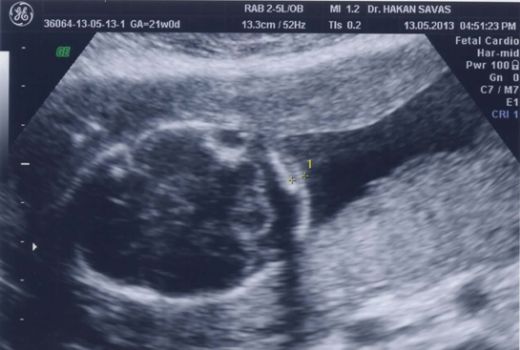

Hamilelik sürecinde yapılan ultrasonografik incelemelerde, fetüsün fiziksel yapısında bazı anormallikler gözlemlenebilir. Bu anormallikler arasında;

Ultrason incelemeleri, Down sendromunun belirtilerini tespit etmekte önemli bir rol oynar. Özellikle 12. haftada yapılan nuchal translucency (ense kalınlığı) ölçümü, risk değerlendirmesinde kritik bir göstergedir. Eğer ense kalınlığı normalden fazla çıkarsa, genetik danışmanlık önerilebilir. Bunun yanı sıra, fetal kalp anormallikleri ve diğer fiziksel gelişim sorunları da ultrason ile gözlemlenebilir.